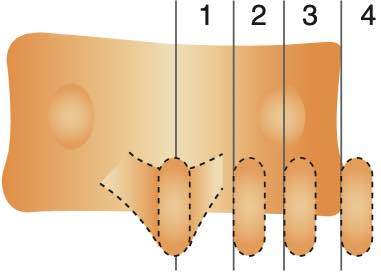

degré rotation vertébrale selon Cobb en fonction de l'épineuse

degré rotation vertébrale selon Cobb en fonction de l'épineuse